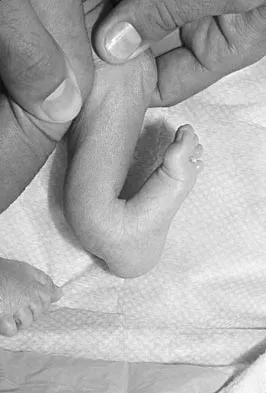

Figure 26 shows the clinical photograph of a patient who has developed a residual limb ulcer following a traumatic transtibial amputation 2 years ago. What is the preferred treatment to resolve the ulcer?

Explanation

The first step in the treatment of an amputation residual limb (stump) ulcer is local wound care and adjustment of the residual limb-prosthetic interface, as well as adjusting prosthetic alignment. Surgical revision should be undertaken only when prosthetic modification is unsuccessful. Murnaghan JJ, Bowker JH: Musculoskeletal complications, in Smith DG, Michael JW, Bowker JH (eds): Atlas of Amputations and Limb Deficiencies, ed 3. Rosemont, IL, American Academy of Orthopaedic Surgeons, 2004, pp 683-700.